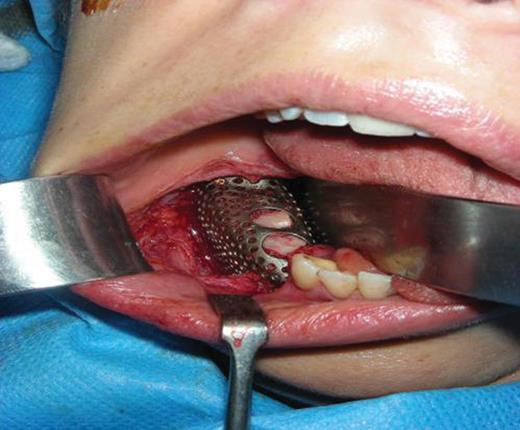

Previously, using CT scans, a titanium construct was made to guide the outline of the bone graft and complete the missing height and width of the mandible [3]. Once fitted to the patients jaw, it was packed with the bone graft and screwed down into position (Fig. 5). A slight groove was made on the mandible to allow space for the inferior dental nerve to lay, so that the construct did not compact the nerve and cause functional problems.

Titanium construct packed with iliac bone graft and screwed into position on the lower mandible